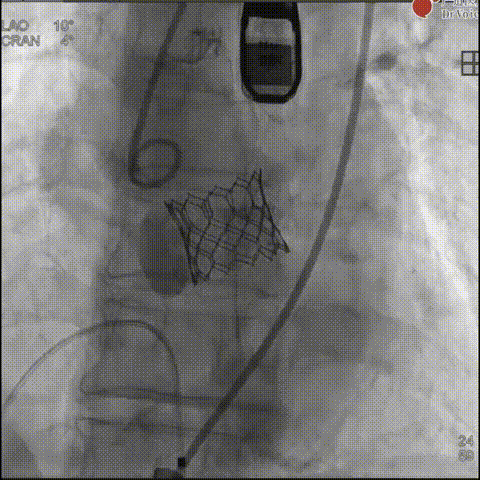

团队首先采用18mm球囊进行预扩处理,为23mm瓣膜输送开辟通路;瓣膜释放阶段,考虑到钙化团块扩张有一定不确定性,为安全起见,通过快速起搏配合减1.5cc容积“downsize”释放策略,实现瓣膜初步精准定位;释放后造影发现瓣周漏,团队随即与GISE主席团专家在线沟通,共同探讨瓣膜后扩优化方案,最终选择增加1.5cc球囊进行后扩,术后瓣周漏明显减少至微量,食道超声确认瓣膜位置、形态及功能均达理想状态,手术取得圆满成功。

瓣膜释放

瓣膜释放后造影

球囊后扩